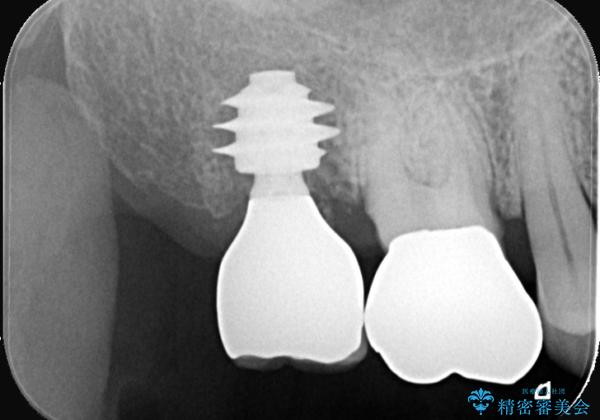

抜歯即時インプラントの利点(共振周波数解析を用いたISQ値の測定により、客観的かつ数値でインプラントの安定性を評価できるようになったため、予知性が高く安全な治療となった。)

●治療期間の短縮

抜歯とインプラント埋入を同時に行うため、抜歯窩の治癒を待つ必要がなく、全体の治療期間を短縮できる。

●骨の吸収抑制

抜歯後は速やかに歯槽骨の吸収が進むが、即時にインプラントを埋入することで骨吸収を抑制できる。